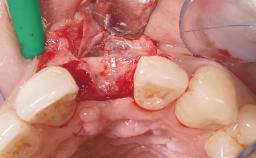

Late Flapless Placement of an Implant in a Maxillary Left Central Incisor Site

Anthony Sclar

A 39-year-old male patient presented with a chief complaint of discomfort and gingival discoloration around his maxillary left central incisor. He was in good general health and was a non-smoker. His past dental history was significant because of the traumatic fracture of tooth 21 in a sporting accident at age 13. Initial dental treatment included endodontic therapy and a full-coverage restoration. The patient became symptomatic 5 years later, when structural failure of the tooth resulted in the dislodgment of the crown. Endodontic retreatment, apical surgery, and post-and-core restoration were performed.

Bone Augmentation Horizontal|Staged

Augmentation Materials Xenogenous|Membrane